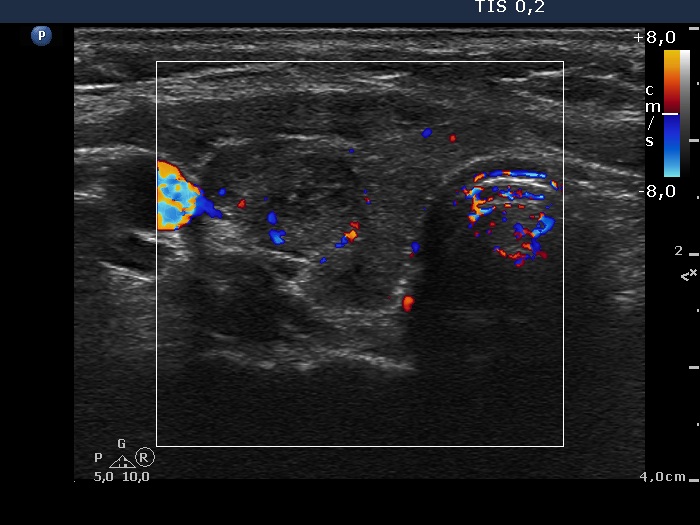

Discrete lesion or nodule in Hashimoto's thyroiditis - case 20 (698) (ultrasonographic picture 6)

Right lobe, another transverse view, color Doppler mode. The vascularization is not specific.